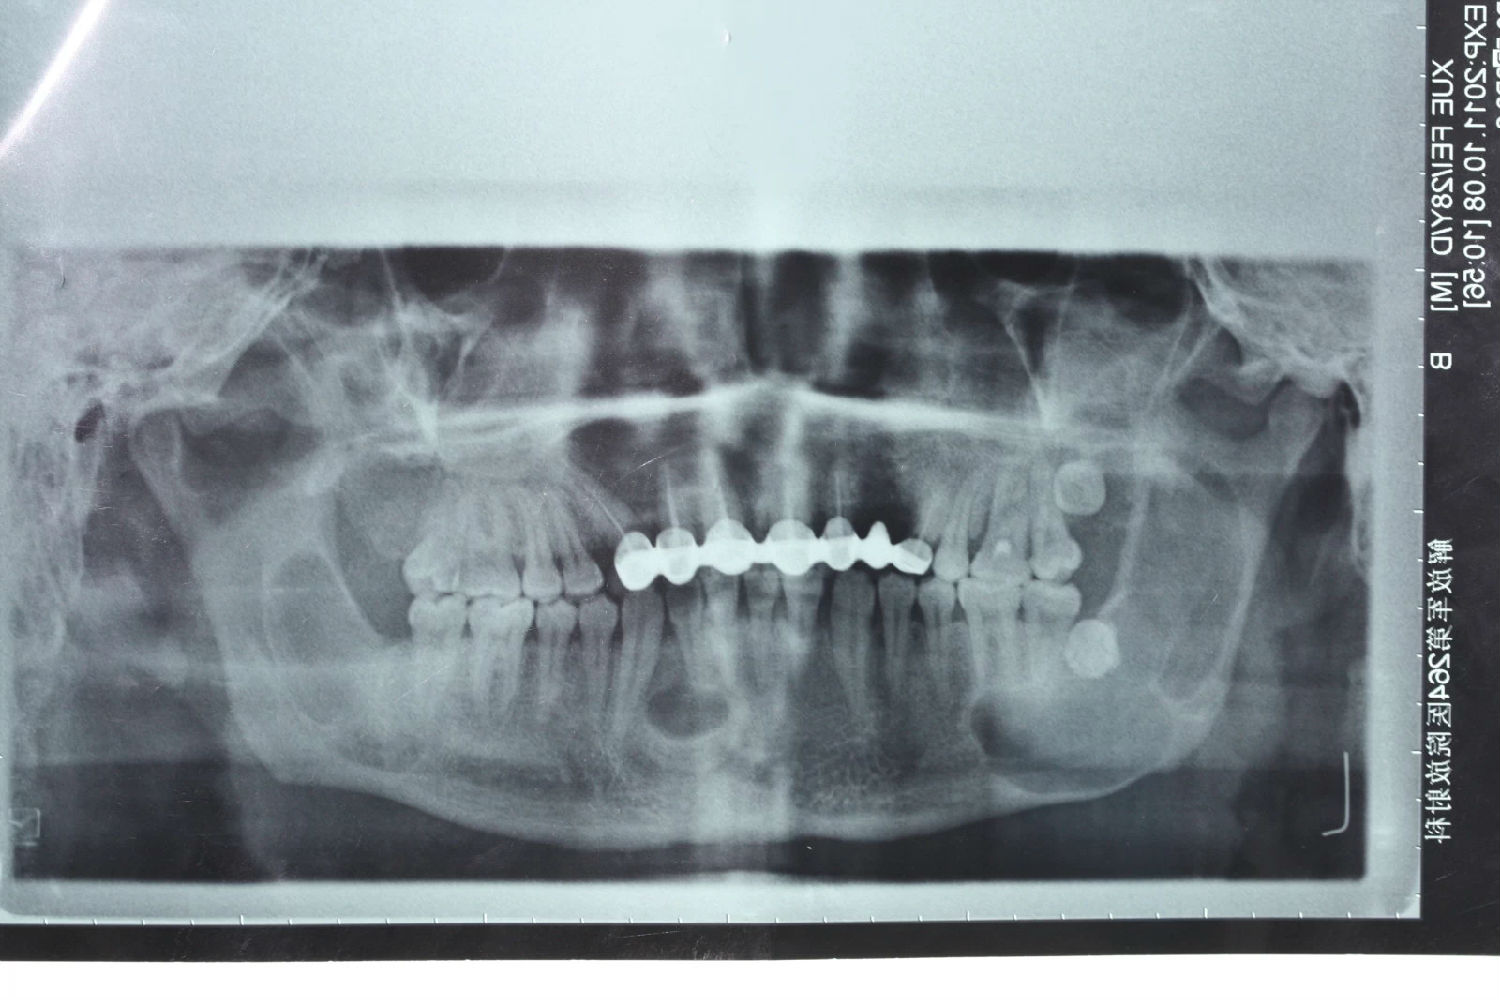

患者男性,主因左面部反復(fù)腫脹半年余,就診后行全景片檢查,發(fā)現(xiàn)下頜骨多發(fā)性囊腫,初步診斷為多發(fā)性頜骨囊腫綜合征,安排住院手術(shù)。